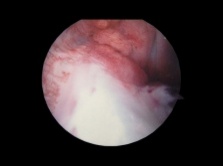

Arthroskopieansicht des vorderen Kreuzbandes

Der obere Ansatz des VKB befindet sich in der Kerbe des distalen Oberschenkels, während der untere Teil des VKB vor der interkondyloiden Eminenz der Tibia ansetzt.